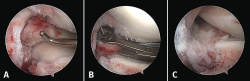

Figure 4. Arthroscopy views from the anterolateral portal, showing bone avulsion with a fragment of the medial root (A), suture advancement through the meniscal root (B), and bone avulsion reduced in its bone bed (C).

Arthroscopy confirmed the diagnosis by visualizing the avulsed root and bone fragment at medial level (Figure 4A) and the radial lesion of the external root (Figure 5). Palpation of both roots evidenced clear instability. The ACL was greatly affected, with subtotal rupture, while the PCL presented correct stability in response to palpation and testing.

The medial root avulsion fracture was repaired using a standard transtibial pullout technique(1,3,6). Suturing required the use of no. 2 FiberWire® (Arthrex, Naples, FL, USA ) through the root with the Knee Scorpion™ system (Arthrex, Naples, FL, USA) (Figure 4B). A FlipCutter® III retrograde reamer (Arthrex, Naples, FL, USA) with a Unicorn Meniscal Root (UMR) guide (Arthrex, Naples, FL, USA) was used to drill a blind tibial tunnel, 6 mm in diameter and 15 mm in length, from the bone bed of the medial meniscus towards the anteromedial tibial cortical layer. The meniscus sutures were retrieved through the trans-bone tunnel with a FiberStick® (Arthex, Naples, FL, USA). The suture was knotted through a metal button, securing correct reduction of the meniscal avulsion (Figure 4C).